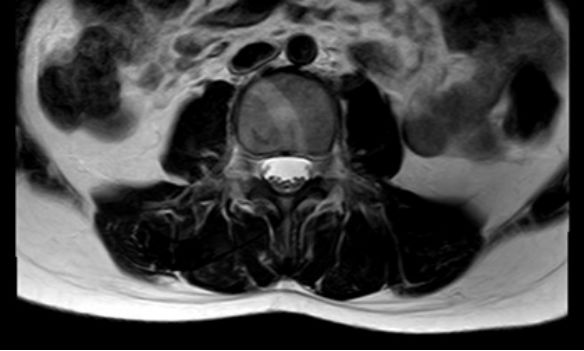

体位及切口:俯卧位,定位腰4/5椎间隙,直切口,约2.0cm(图4)。切开棘上韧带至黄韧带,暴露硬脊膜,再切开硬脊膜探查椎管内:明确脂肪变的终丝,游离周围神经,电凝终丝血管,切断终丝。缝合硬膜及切口(图5)。

图5. A切开棘上韧带至黄韧带,暴露硬脊膜,B再切开硬脊膜探查椎管内:C明确脂肪变的终丝,游离周围神经,D电凝终丝血管,切断终丝。E缝合硬膜及切口